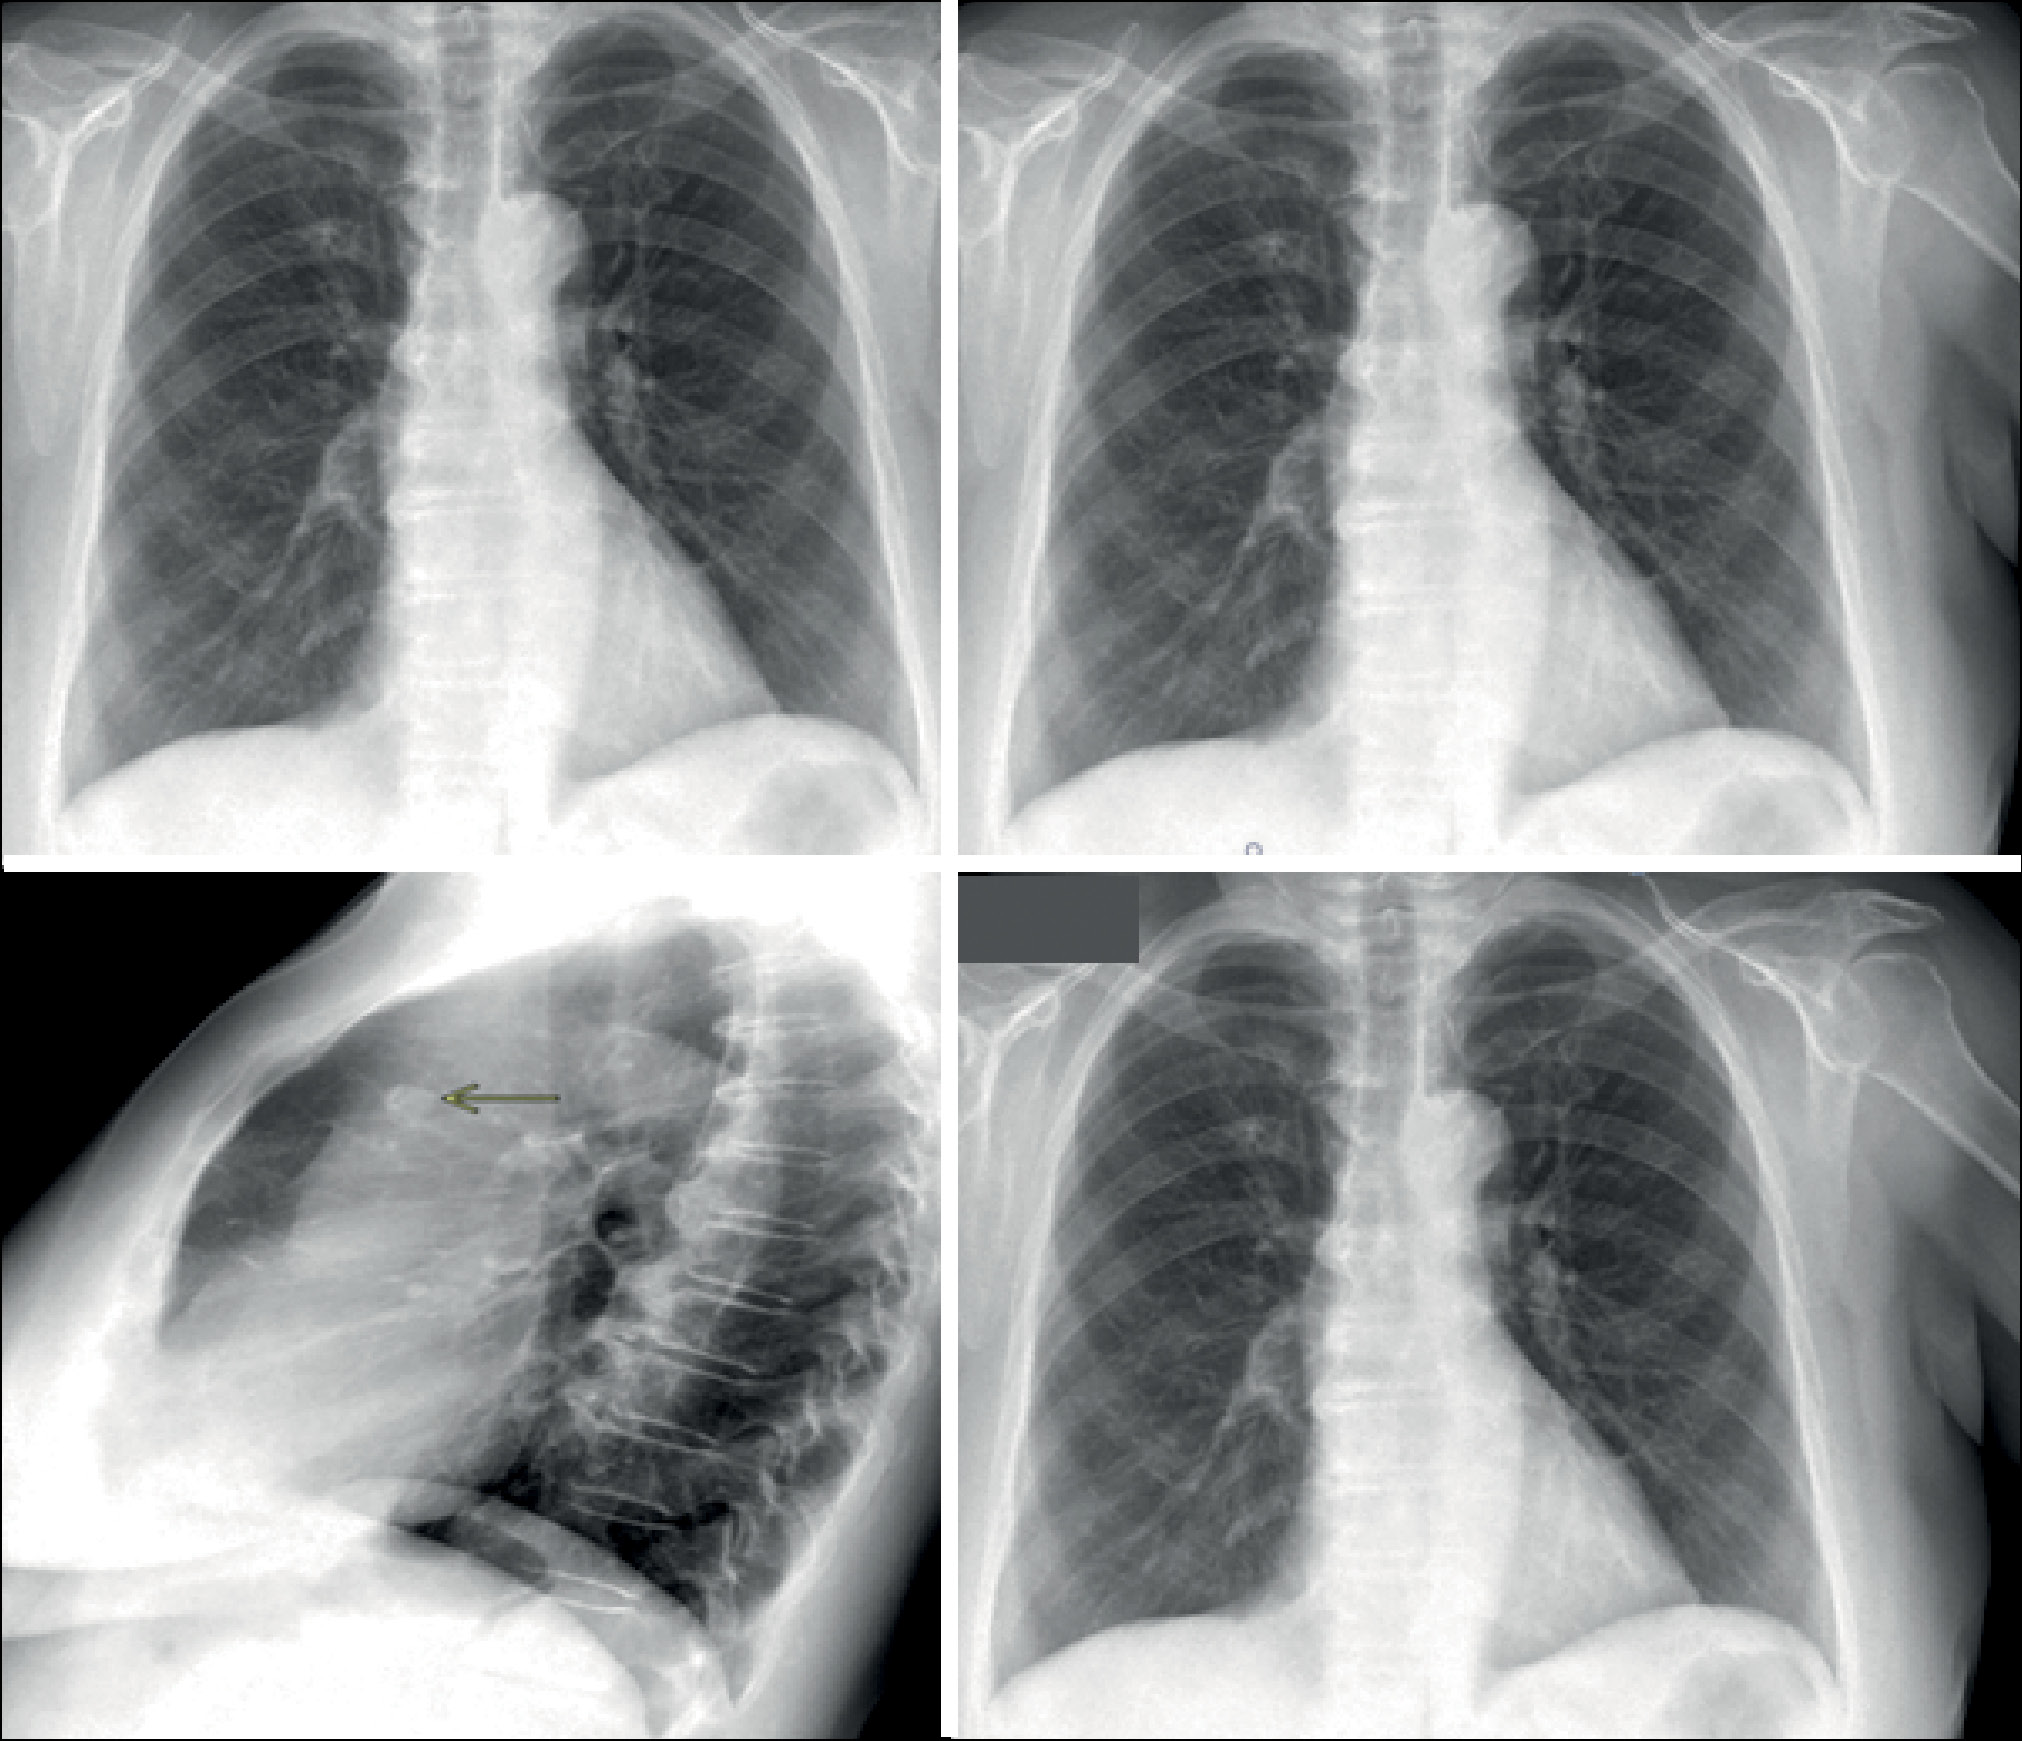

Следующим аспектом данной проблемы является то, что оценка рентгенограмм органов грудной клетки осуществляется ПО на основе ТИИ только в прямой проекции и, учитывая наличие «слепых зон» на прямых рентгенограммах (базальные и прикорневые отделы лёгких, задние косто-диафрагмальные синусы), не позволяет ИИ-сервисам сделать достоверный вывод о наличии либо отсутствии патологических изменений в указанных зонах [17, 23]. В данном исследовании был выявлен один случай ложноотрицательного заключения ПО на основе ТИИ при наличии у пациента грыжи пищеводного отверстия диафрагмы (рис. 7), а также один ложноположительный результат, связанный с ортоградным расположением лёгочного сосуда, который один из ИИ-сервисов обозначил как лёгочный узел.

Рис. 7. Грыжа пищеводного отверстия диафрагмы, не обнаруженная программным обеспечением на основе технологий искусственного интеллекта за тенью сердца.

Выявлен также случай необнаружения очаговой тени, которая в прямой проекции проецируется на тень средостения и может быть выявлена только на снимке в боковой проекции (рис. 8).

Рис. 8. На боковой проекции визуально определяется очаг в проекции верхней доли (все программные обеспечения на основе технологий искусственного интеллекта закономерно его не определили ввиду обработки только прямой проекции).

В другом случае ИИ-сервис, опять же по причине невозможности обработки боковой проекции, не определил фиброзные изменения (рис. 9).

Рис. 9. На боковой проекции определяются фиброзные изменения в заднем косто-диафрагмальном синусе справа, которые не видны на прямой проекции (сервис искусственного интеллекта их не определил ввиду обработки только прямой проекции). Аналогично данным изменениям сервис может «пропустить» минимальный плевральный выпот.